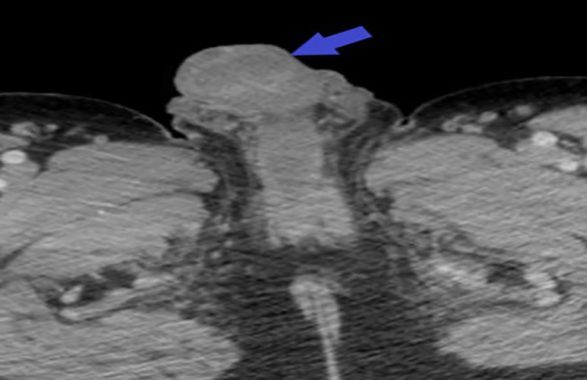

Ghazanfar si è trovato davanti un trentacinquenne arrivato al Pronto Soccorso lamentando dolori terribili al pene e allo scroto: l’organo era scuro, gonfio, ulcerato e trasudava un liquido dall’odore nauseante.

L’uomo tre giorni prima si era iniettato cocaina sulla vena dorsale del pene: era un utilizzatore abituale della droga e ha ammesso di aver utilizzato la stessa vena almeno due volte nelle due settimane precedenti “senza alcuna complicazione”.

La terza volta non è stato così fortunato: la cocaina scatena una forte infiammazione nei vasi sanguigni e può portare alla cancrena e quindi alla morte dei tessuti, inoltre come spiega Ghazanfar “spesso viene tagliata con un farmaco, il levamisolo, che potenzia l’infiammazione nei vasi sanguigni. La cocaina viene spesso iniettata, oltre che sniffata o fumata; la vena del pene può sembrare una scelta insolita ma non lo è poi così tanto, molti tossicodipendenti utilizzano vari siti di iniezione quando quelli “classici”, come le vene del braccio, sono inservibili perché troppo danneggiati a causa degli effetti dannosi della droga”.

L’uomo ha rifiutato di sottoporsi alla chirurgia per eliminare il tessuto morente, così per salvare l’organo è stato curato con un cocktail di antibiotici per via endovenosa per cinque giorni, seguiti da altri cinque giorni di antibiotici per via orale; nel frattempo hanno medicato il tessuto ulcerato e pian piano le condizioni dell’organo sono migliorate.